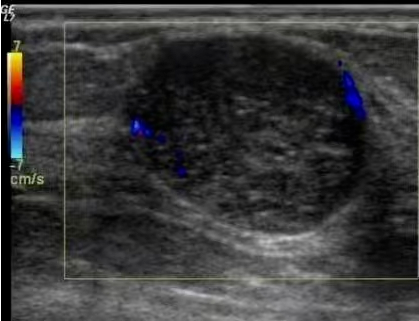

乳腺超声检查:灵活便捷,贴心呵护

乳腺超声检查,以其操作灵活、安全便捷的显著优势,成为众多女性的首选。它特别适用于孕妇、哺乳期女性、年轻未婚女性以及术后复查的患者群体,让这些特殊人群也能安心进行乳腺检查。

不仅如此,超声还能为乳腺疾病的穿刺活检或术前定位提供精准引导,大幅提高操作的准确性,为后续治疗提供有力支持。不过,它也有一定局限性,对乳腺癌微钙化的检出能力稍显不足,敏感性不如钼靶,所以常需与 X 线检查相结合。同时,超声检查的诊断准确性受操作者经验影响较大,对可疑淋巴结的显示也不够全面。但即便如此,它在乳腺健康检查中依然占据着不可替代的重要地位。